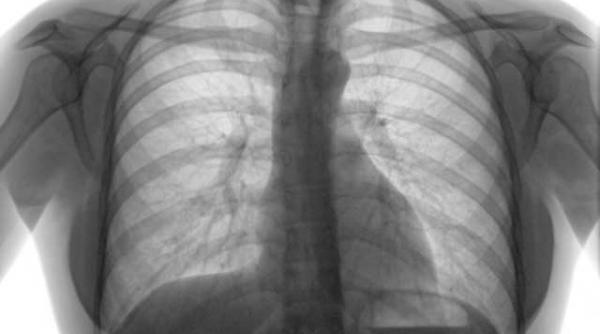

Trei „medicamente” pentru tratarea bolilor cardiace: activitatea fizică, reducerea greutăţii şi renunţarea la fumat